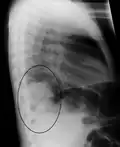

AP CXR showing left lower lobe pneumonia associated with a small left sided pleural effusion -

AP CXR showing right lower lobe pneumonia -

AP CXR showing pneumonia of the lingula of the left lung -

Right upper lobe pneumonia as marked by the circle. -

Left upper lobe pneumonia with a small pleural effusion.

Right lower lobe pneumonia as seen on a lateral CXR